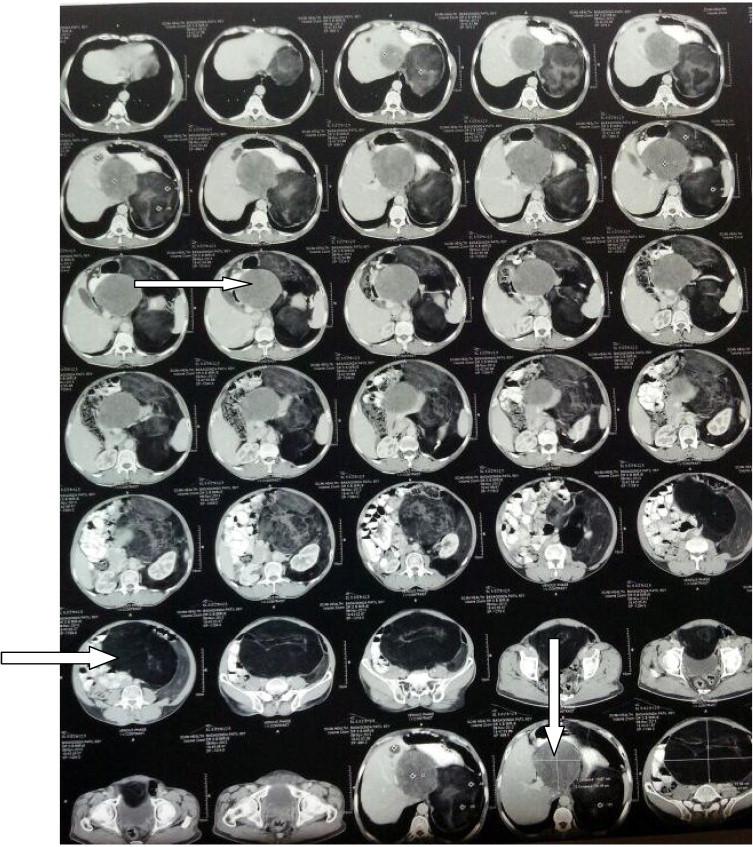

PRESENTATION OF CASE

A 60-year-old male presented with left sided abdominal distension and pain since 4 months, ultrasonography and computerized tomography abdomen was suggestive of multiple well-defined fat density lesions in the lower abdomen and pelvis. USG guided fine needle aspiration cytology was conclusive of a spindle cell lesion. Exploratory laparotomy was performed and multiple major fat tissue swellings were excised. Histopathology confirmed it to be spindle cell type of lipoma.

病例介绍

一名60岁男性,4个月来出现左侧腹胀和疼痛,腹部超声和计算机断层扫描显示下腹部和骨盆有多个边界清晰的脂肪密度病变。超声引导下细针穿刺细胞学检查确诊为梭形细胞病变。进行了剖腹探查术,切除了多个主要的脂肪组织肿块。组织病理学证实为梭形细胞型脂肪瘤。